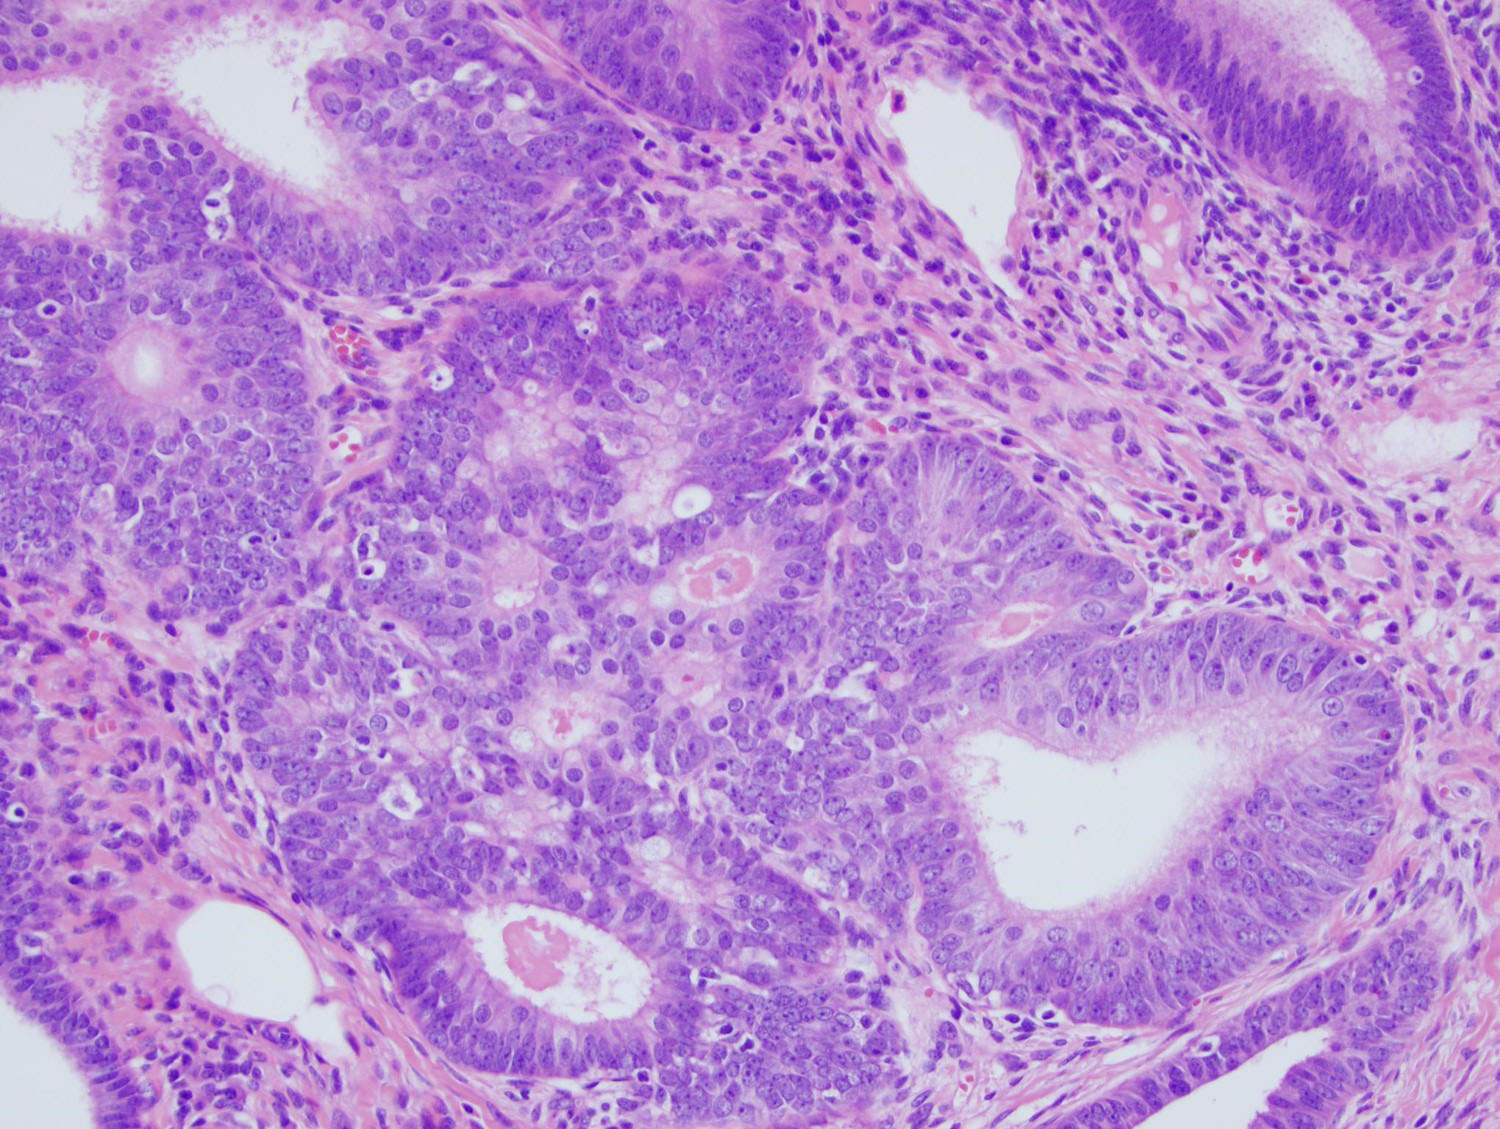

Microscopic examination of the sigmoid polyp demonstrated complete replacement of the normal colonic mucosa with infiltrating angulated and irregular glands lined by benign pseudostratified columnar epithelium, some of which were cystically dilated (Figures 2-4). Surrounding these glands was a characteristic spindle cell stroma admixed with inflammatory cells and prominently dilated vasculature. Immunohistochemical (IHC) stains were performed. The glands were negative for CDX2 and CK20 (Figures 5 and 6), while positive for PAX8 (Figure 7) and focally strongly positive for CK7 (Figure 8). The surrounding stroma was focally positive for CD10 (Figure 9).